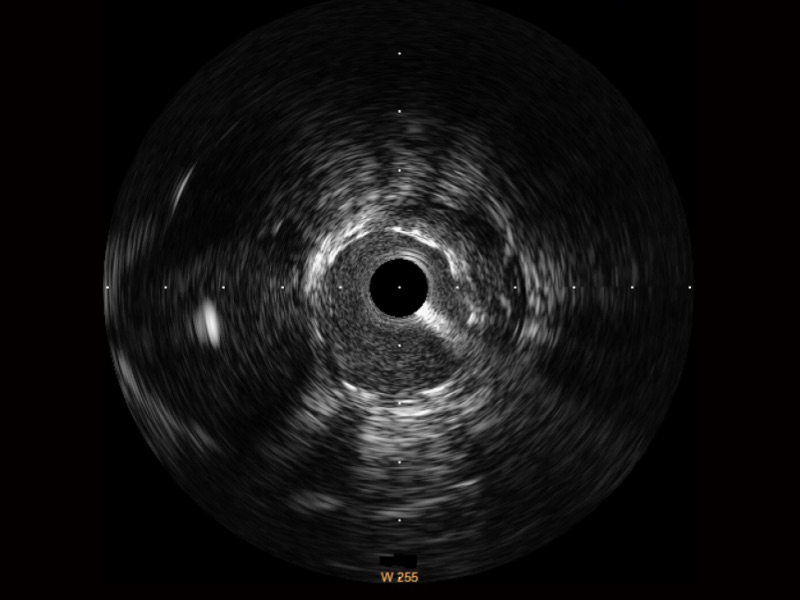

狗万官方网站超宽频成像技术覆盖20-80MHz1或20-90MHz2频率范围, 提供优异的分辨力同时也保证充足的穿透深度

对比传统IVUS导管成像,狗万官方网站宽频IVUS图像的近场支架梁显影更细腻,远场中膜外血管仍清晰可辨,兼顾远中近,兼顾分辨力与穿透深度